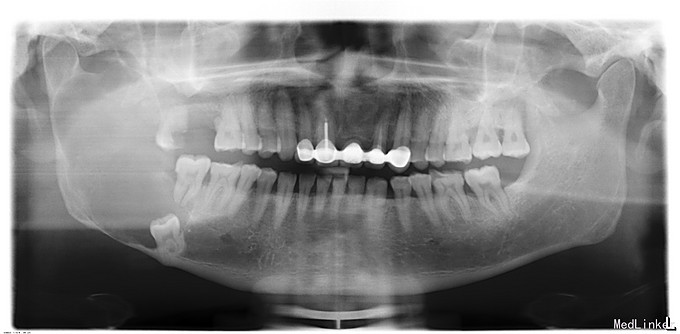

发现下颌骨肿物1年余,中年男患者,慢性病程。患者于1年余前发现右侧下颌肿物,不伴疼痛,表面皮肤无破溃,无下唇麻木。今为进一步治疗来我院就诊,门诊以“右下颌骨肿物”收入院。

双侧颜面部不对称,右下颌隆起,约4cm*7cm,表明皮肤无异常,皮温无升高,质地硬,边界尚清,无压痛,无乒乓球样感,无左下唇麻木,无张口受限,开口度、开口型正常,双侧髁突动度一致,开闭口未闻及关节明显弹响音。口内检查:右侧下颌肿物,下颌骨颊侧隆起,边界清,无压痛,表面粘膜无破溃,双侧头颈部有扪及明显肿大淋巴结。

入院诊断:右下颌骨肿物,出院诊断: 右下颌骨角化囊性瘤?手术名称:右下颌骨肿物开窗术+切取活检术+18、47、48拔除术